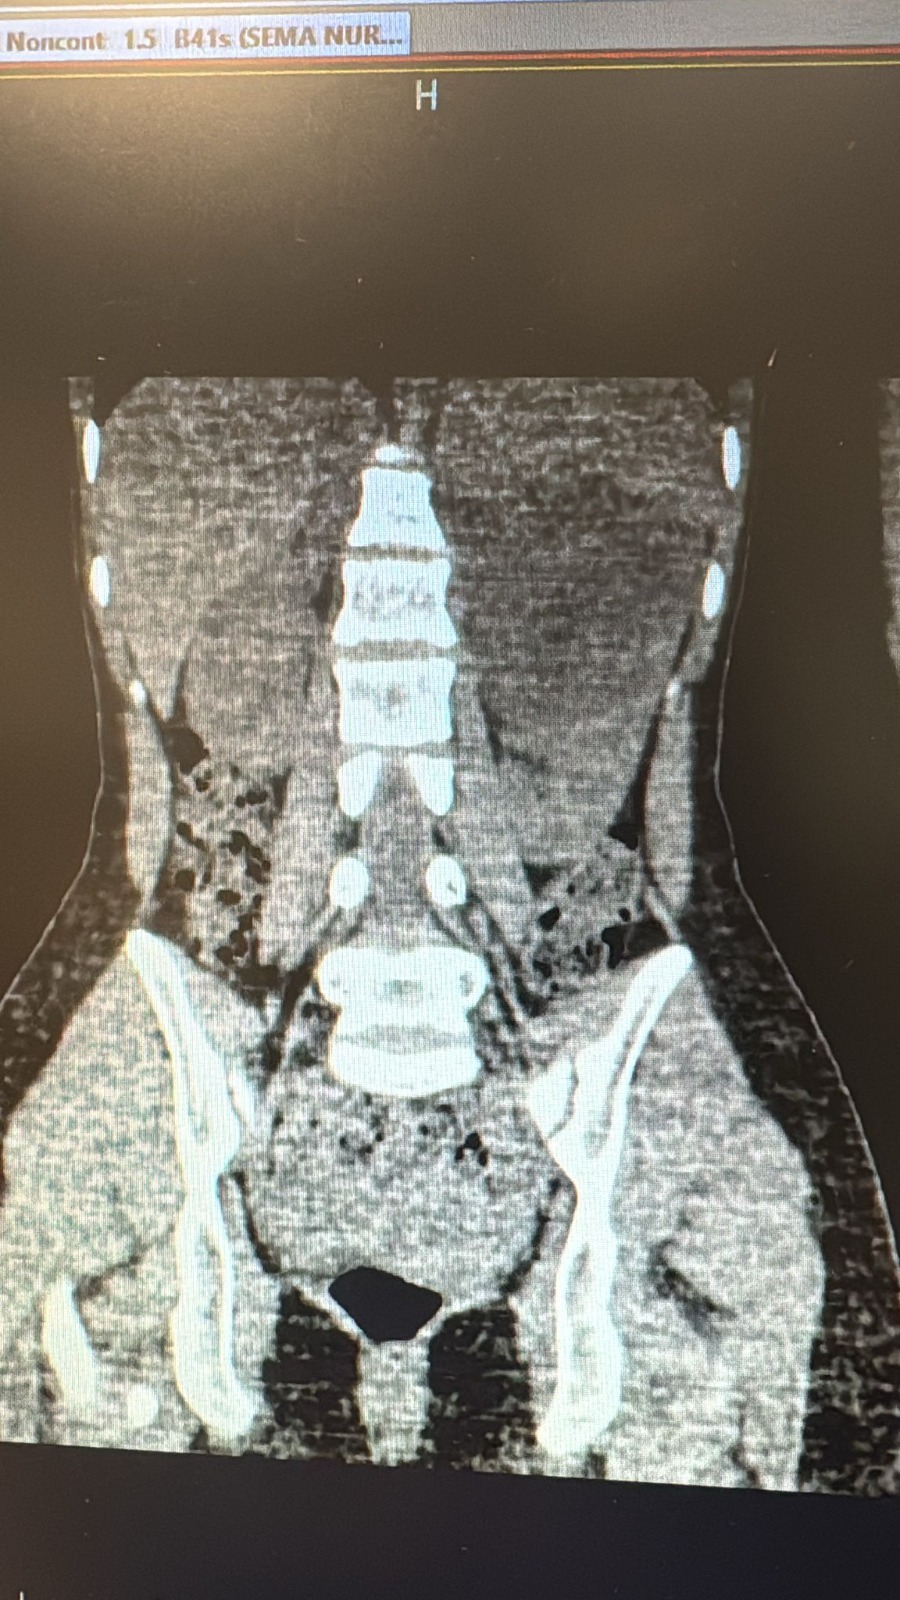

Hastanede yapılan gerekli tetkik ve muayenelerin ardından kistin cerrahi yöntemle çıkarılmasına karar verildi. Viranşehir Devlet Hastanesi’nde gerçekleştirilen başarılı ameliyatla, 10 cm boyutundaki böbrek kisti laparoskopik (kapalı) yöntemle, 2 adet 5 mm ve 1 adet 10 mm’lik kesi kullanılarak çıkarıldı. Bu sayede hastamız, büyük boyutlu kistine rağmen açık cerrahiye gerek kalmadan tedavi edilmiş oldu.

Ameliyat sonrası takiplerinde herhangi bir komplikasyon gelişmeyen hasta, şifa ile taburcu edildi.Sol böbreğinde 10 cm boyutunda kiste bağlı semptomları bulunan hastanın ameliyatı; Anestezi Uzmanı Uzm. Dr. Erdi Karahan liderliğindeki anestezi ekibi, Genel Cerrahi Uzmanı Op. Dr. Burak Sevinç’in desteğiyle, Üroloji Uzmanları Op. Dr. Özlem Başgut ve Op. Dr. Ahmet Furkan Sarıkaya tarafından başarıyla gerçekleştirildi.